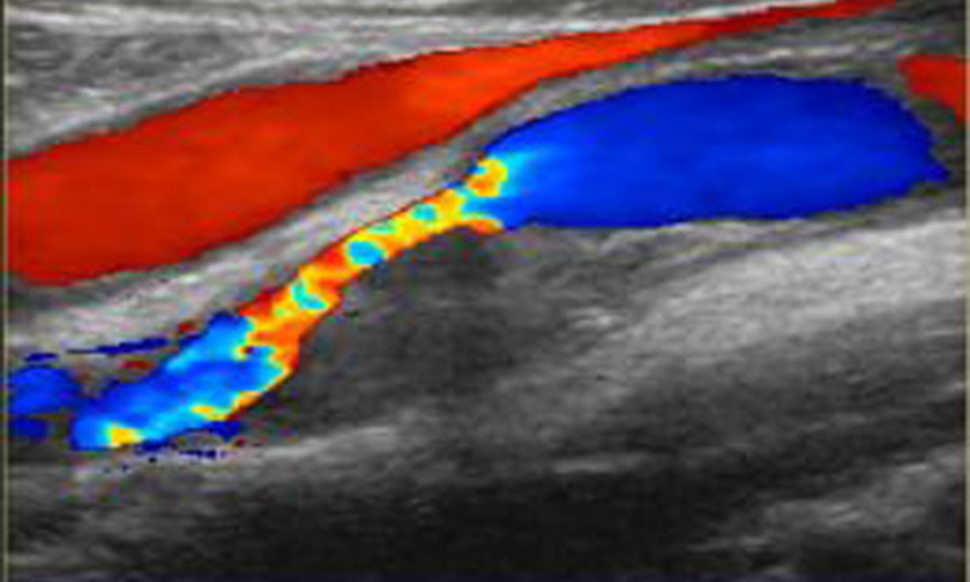

Дуплексное сканирование схоже с допплерографией, однако, в отличие от последней, оно позволяет не только оценить кровоток, но и проанализировать состояние стенок сосудов. Цветовое дуплексное сканирование брахиоцефальных артерий дополнительно предоставляет информацию о проходимости сосудов с использованием цветовой кодировки.

Если к этим двум режимам добавляется третий – ЦКД (цветовое допплеровское картирование), то такое исследование называется триплексным сканированием. В этом случае проблемные участки будут обозначаться красным цветом, а здоровые – синим.